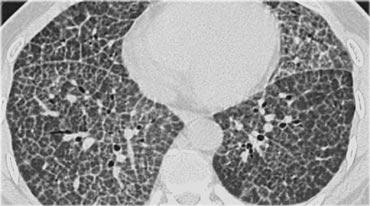

Bệnh nhân này nhập viện với triệu chứng khó thở cấp tính và phim X-quang ngực bình thường (không trình bày).

HRCT lúc nhập viện (trái) cho thấy các vùng kính mờ theo phân bố tiểu thùy.

HRCT kiểm tra mười ngày sau (phải) cho thấy các tổn thương đã thoái lui hoàn toàn mà không cần điều trị.

Các tổn thương được cho là do viêm phổi quá mẫn.